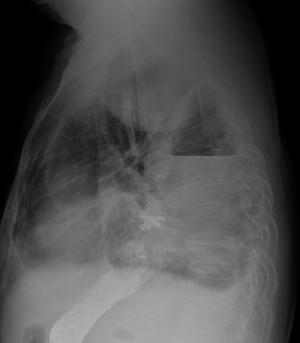

患者、男,66y,食道贲门ca术后13多天,不规则发热,来科照片:

考虑:1、食道胃胸腔吻合术后改变;

2、左侧液气胸;

3、图像欠清,右侧难以观察。

考不考虑左侧下肺背段脓肿?,那个气液平好像在肺内。

另外左侧肺尖区高密度影。是胸膜增厚吗?

1、胸腔胃,术后改变。液平面为胃泡影。

2、左侧胸膜增厚。

1、观察钡剂未流入气液平面内,考虑左后胸腔内包裹性气液平面改变

2、左侧胸壁包裹性胸腔积 液 结合临床病程行ct检查,

这是北京专家的会诊,(二炮总医院远程会诊结论)